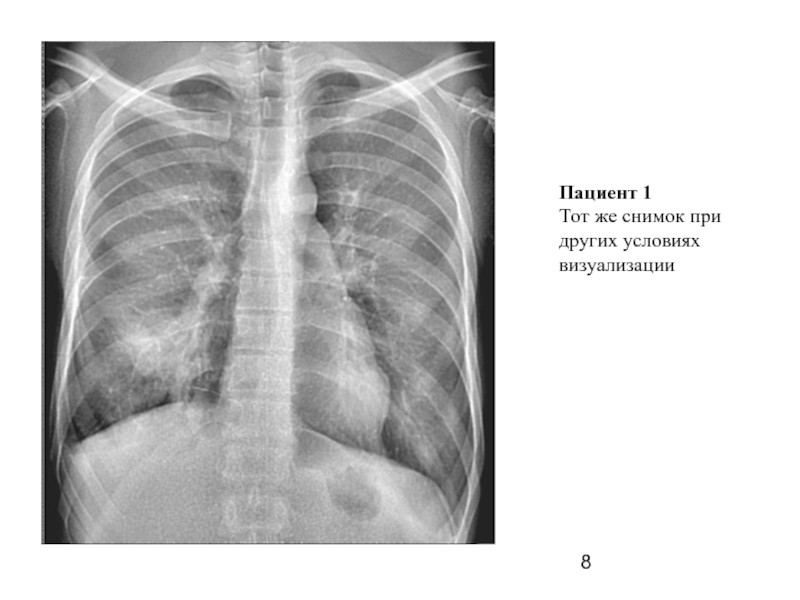

Слайд 8Пациент 1

Тот же снимок при других условиях

визуализации

Слайд 6Пациент 1

(прямой снимок)

Описание:

справа в S-10 участок инфильтрации легочной ткани без четких

контуров.

Правый корень расширен, структурность снижена. Справа на границе нижнего

средостения на уровне D-10 определяется инородное тело металлической плотности, линейной формы, длинной 31 мм, окруженное

плевро-медиастинальными

спайками.

Заключение:

правосторонняя сегментарная S-10 пневмония. Металлическое инородное тело средостения (плевральной полости?) справа.